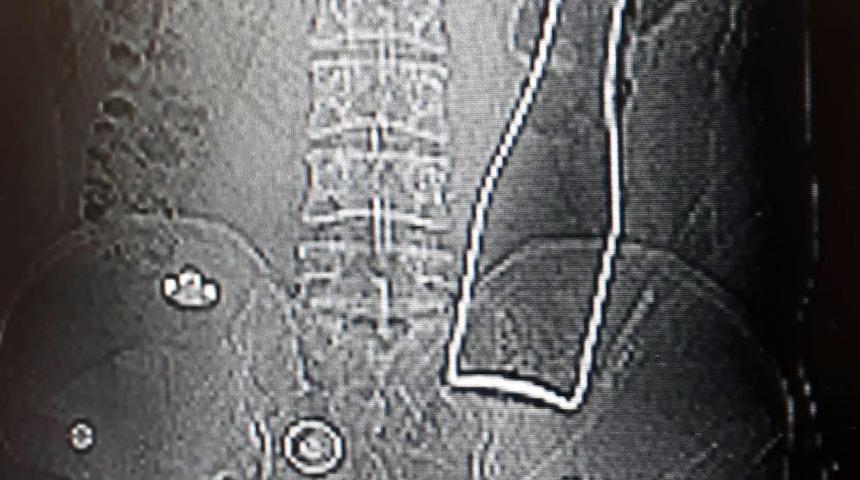

Karaman'da karın ağrısı şikayetiyle gittiği hastanede çekilen röntgen filminde kalın bağırsağında şişe olduğu ortaya çıkan Afgan A.E.'nin (27) ifadesinde, ''Olay günü banyoda duş alırken yanlışlıkla bu olay gerçekleşti'' dediği ortaya çıktı.

Karaman Eğitim ve Araştırma Hastanesi'ne, 28 Haziran Pazar gecesi gelen A.E., karın ağrısı şikayeti olduğunu söyledi. Bunun üzerine röntgen filmi çekilen gencin kalın bağırsağında şişe olduğu görüldü. Makattan girdiği belirlenen şişe, yaklaşık 1 saat süren ameliyatla çıkarıldı.